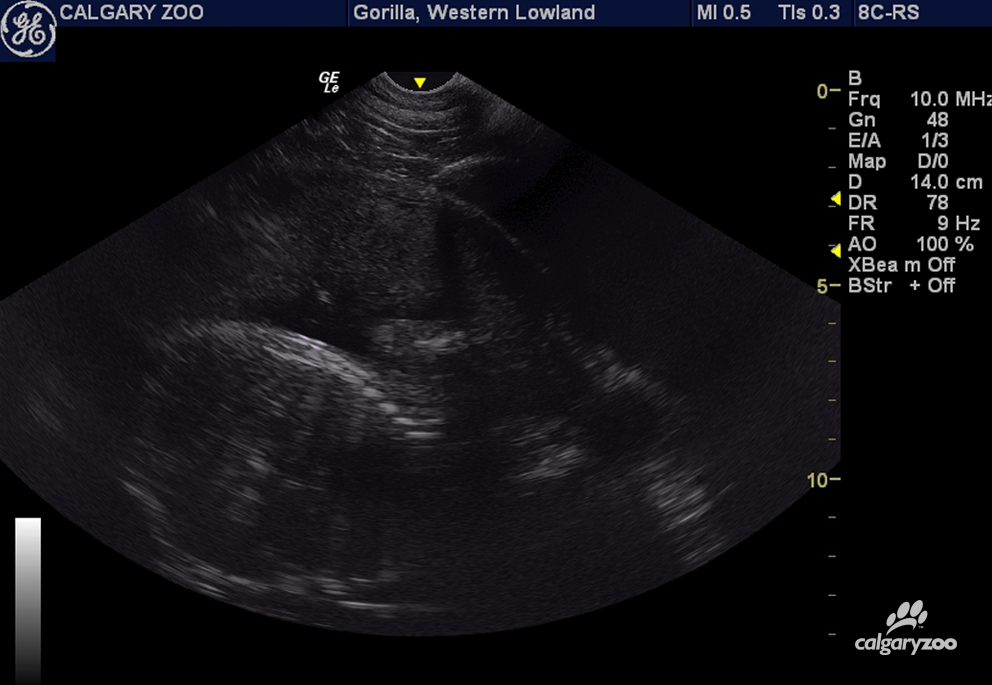

“This includes specialized training, conducting regular ultrasounds, behavioural analysis and close monitoring by the zoo’s veterinary staff,” explained the zoo in a news release.

The Calgary Zoo’s 14 year-old female gorilla Kioja is pregnant and expecting her first offspring in early March 2016. The Calgary Zoo